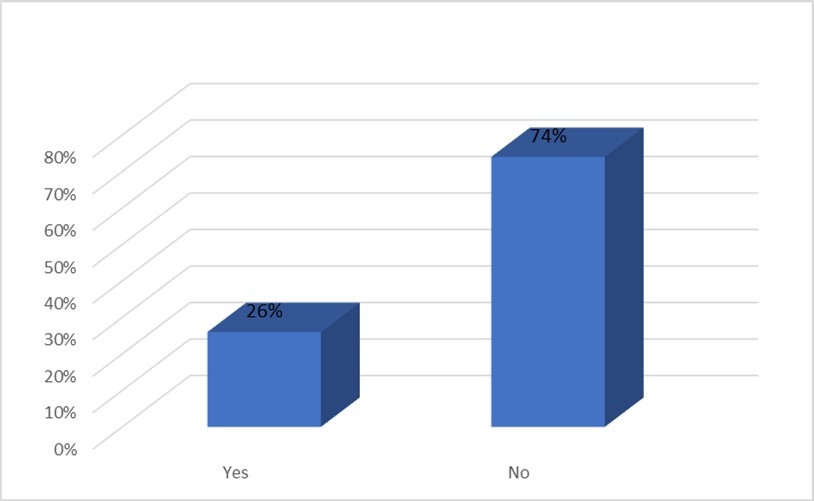

Of 100 Patients, 26% had hypoxemia. Those patients, who had PaO2 less than 70 mmHg were considered hypoxemic. Figure 2

Figure 2.Distribution of COPD patients according to development of hypoxemia (n=100)

The patient who had PaO2 less than 70 mmHg were considered hypoxemic. Among 100 COPD patients, almost 87% patients with microalbuminuria were hypoxemic. Only 13% patients were free from hypoxemia who had microalbuminuria. Patients without microalbuminuria had no history of hypoxemia. There is significant relation exists between hypoxemia and presence of microalbuminuria (p<0.5). Table 5

Microalbuminuria is an important risk factor for cardiovascular diseases. Microalbuminuria may be seen due to hypoxemia in patients with chronic obstructive pulmonary disease (COPD)22. This study was designed to assess the prevalence of microalbuminuria and its relation with hypoxemia in patients with COPD. Total 100 patients were included. The mean age was 58.16±5.4 years, ranging from 50 to 74 years. This is concordant with the findings of Sujay and Gajanan 23 who found a mean age of 59.67±5.60 years in their study. Majority patients belonged to age group 55 to 60 years (42%), followed by 61 – 65 years (28%). This is slightly different from the findings of Alam et al 24 who reported that majority COPD patients were aged between 60 – 69 years (27.5%) followed by 50 – 59 years (13.6%). This difference may be due to age grouping between the reports. But both the studies confirm that age is a well established risk factor for COPD as increasing prevalence of COPD is noted in higher age groups 79. In this study 82% patients were male and 18% were female. Sujay and Gajanan 23 and Bulcan et al 25 reported a similar high prevalence of male in their study. The high prevalence of male among COPD patients can be linked to high prevalence of tobacco use among male adults in Bangladesh as noted by Khandker et al 26. Majority patients were day labourer (30%), farmer comprised 16% and businessman comprised 16% of study population. Alam et al24 noted that COPD prevalence in Bangladeshi adults were about three times higher in manual workers than non-manual workers. This explains the high prevalence of day labourer and farmers in this study. Slightly more than half of the patients (54%) came from rural area. This was also noted in the study by Alam et al 24 in Bangladesh and Zhong et al 27 in China. Such community variability of COPD can be explained by connecting occupations like farmer living in rural area, use of biomass fuel in the village community and smoking habit among manual workers. Majority patients were illiterate (34%), followed by 26% patients appeared at primary education. This higher prevalence of lower educational qualification in COPD patients was also found in the study by Alam et al24. Majority of the patients came from lower income categories in this study. A similar finding was elicited by Alam et al24 in their study COPD prevalence study among the adult population of Bangladesh. In the present study, 80% of patients were active smokers. Among them, 52% of patients smoked 26 to 35 pack-years. The mean smoking pack-year was 29.62±6.41 years. A similar mean pack-year of 28.91±6.13 was reported by Sujay and Gajanan in their study entitled “Clinical significance of microalbuminuria and hypoxemia in patients with chronic obstructive pulmonary disease” 23. On the other hand Casanova 28 found a high mean pack-year of 58±25 among COPD patients in their study entitled "Microalbuminuria and hypoxemia in patients with chronic obstructive pulmonary disease”. In the present study 38% patients had severe COPD (GOLD stage III), 32% had moderately severe COPD (GOLD stage II), 16% had mild disease (GOLD stage I) and 14% had very severe disease (GOLD stage IV). In contrast Sujay and Gajanan (2) reported 25% GOLD Stage I, 21% Stage II, 20% Stage III, and 34% Stage IV COPD cases in their study. Stage IV cases were higher in their study in comparison to present study. Alam et al (3) in their study entitled “Prevalence and determinants of chronic obstructive pulmonary disease (COPD) in Bangladesh” found that among 13.5% cases of COPD 8% had GOLD stage II disease, 2.7% had stage I disease, 2.3% had stage III disease and 0.6% had Stage IV disease. Their study was community based and depicts the proportion of COPD severity in the community. In contrast the present study as well as the study by Sujay and Gajanan23 was conducted in a hospital setting where advanced cases COPD cases usually get admitted. Microalbuminuria (MAB) was found in 30% patients. This is concordant with other studies: Mehmood and Sofi (8) reported MAB in 20.6% COPD patients and Sujay and Gajanan23 reported MAB in 30% patients. Casanova27 compared presence of MAB in COPD patients and non-COPD smoker controls and found higher prevalence of MAB among COPD patients. In a study by Bulcun et al., 25 it was found that the prevalence of MAB is 39%. In the present study, majority of COPD patients with MAB had GOLD stage of III (40%) and Stage IV (33%), and this association was statistically significant; P = 0.025. In a study by Casanova et al., 28 any association between MAB and spirometric severity of COPD was not observed. Mehmood and Sofi 29 found that COPD patients with MAB had significantly lower levels of FEV1which is similar to finding of present study. In the present study COPD with MAB patients had mean FEV1 % predicted of 37.40±14.48which is significantly lower than those without MAB (59.34±22.78). 26% patients were in hypoxemic status in this study. MAB was significantly more in COPD patients having PaO2 below 70 mm Hg as compared to COPD patients having PaO2 above or equal to 70 mmHg (86.7% vs. 13.3%, respectively, P < 0.001), which indicates COPD patients with MAB were more hypoxemic. In a study by Sujay and Gajanan a Casanova et al. 28 and Mehmood and Sofi, 29 patients with COPD and MAB were more hypoxemic than those without MAB, and it was inversely related to PaO2.